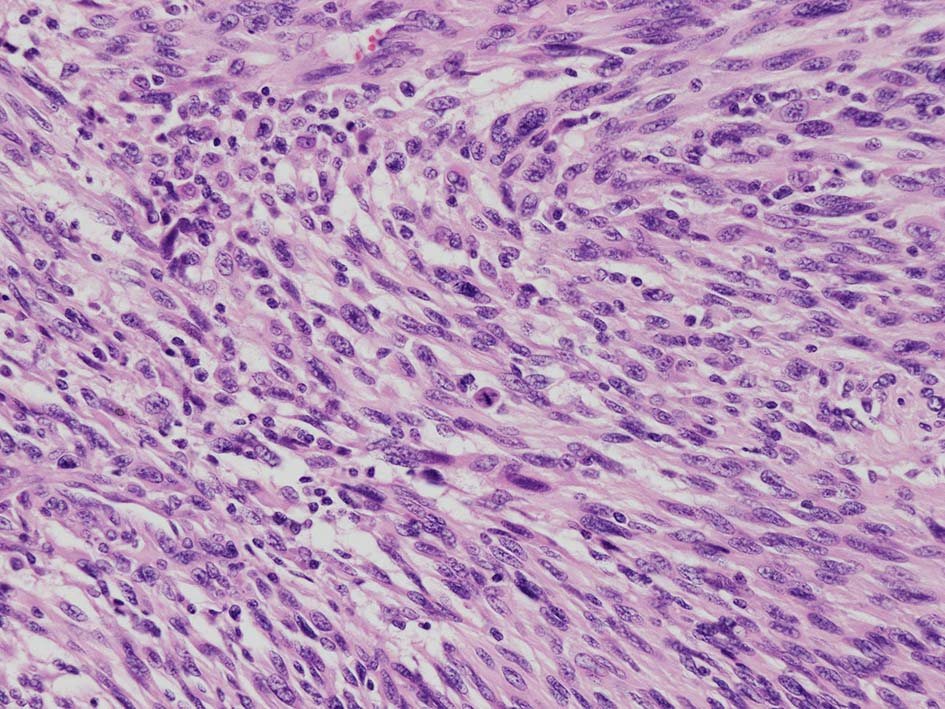

紡錘形異型メラノサイトが著明な間質反応(desmoplasia)を伴い増殖する特殊な色素性病変。*1. desmoplastic neurotropic melanomaは, desmoplastic melanomaのうち神経向性(neurotropism:神経周囲侵襲像)がめだつものでReedら*2が最初に報告した。

いずれも腫瘍細胞の異型性が乏しく, 背景の間質反応がめだつこと, メラニンの存在が目立たないことが特徴である。

病理組織所見*4

再発腫瘤病変の組織像